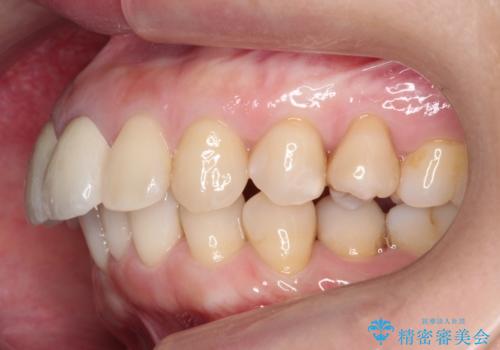

変色した前歯をセラミックでひっこめたい

- 前歯の色と、前突感を気にして来院。

全体的な矯正治療をすすめましたが、ご希望されませんでした。

左上の前歯の神経が失活(死んでいた)していたため、神経の治療を行いました。

また、右上の前歯を下げるため、便宜的に神経を取る治療を行いました。

結果、気になっていた色と角度が良くなり、大変喜んでいただけました。

右上1はひっこめた量が大きかったため、反対側の1番と切端をそろえるのに、多少長さは長くなりました。

右上2、左上2の補綴も提案はしましたが、最小限の本数で行っていくことになり、右上2の捻転(歯のねじれ)はそのままとなっております。